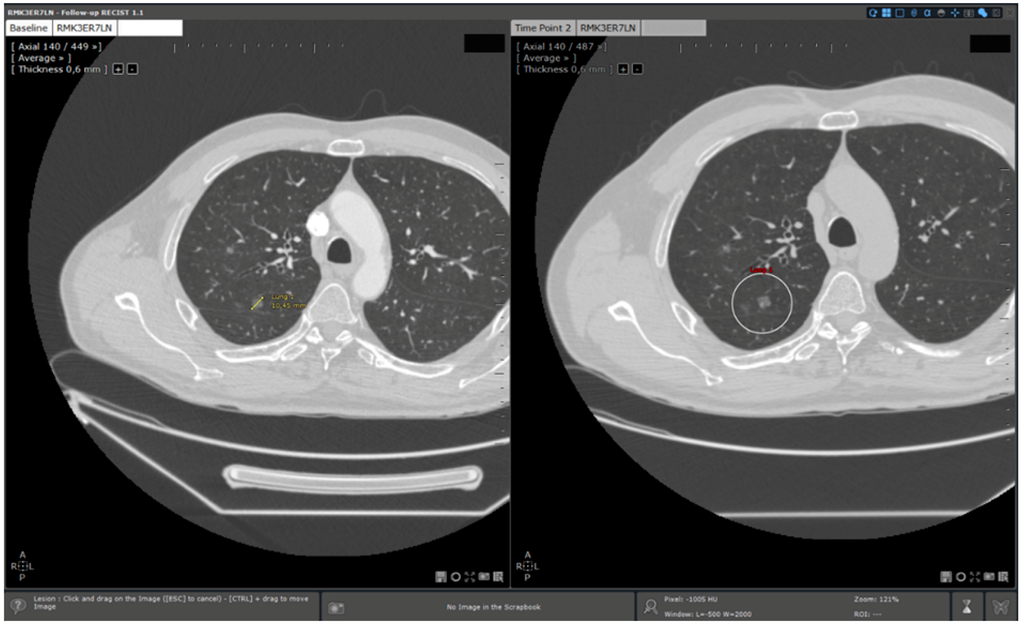

- Standard reading: Manual determination of RECIST response using a standard viewer (Myrian®, Intrasense, France) without specific options dedicated to oncologic follow ups. This reading is called “manual reading” in the rest of the article.

- Reading with dedicated software: Determination of RECIST response with the dedicated application for oncologic follow ups, Myrian® XL-Onco, with specific functionalities:

| Step 2 | Baseline study opening | Manual | Automated |

| Step 3 | Target localisation on baseline study | Manual | Automated |

| Step 4 | Target localisation on follow up study | Manual | Automated |

- 3D target matching technology to facilitate lesion localisation in the follow up study.